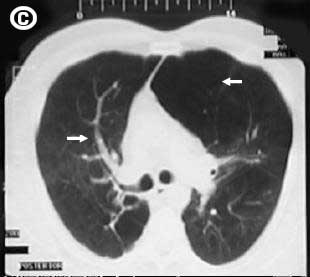

Corte Tomográfico

Corte tomográfico C, a nivel carina traqueal, observe el reforzamiento de la trama vascular e hilear pulmonar, el aspecto trabecular pulmonar y la gran bula pulmonar izquierda que ocupa el espacio retro esternal.